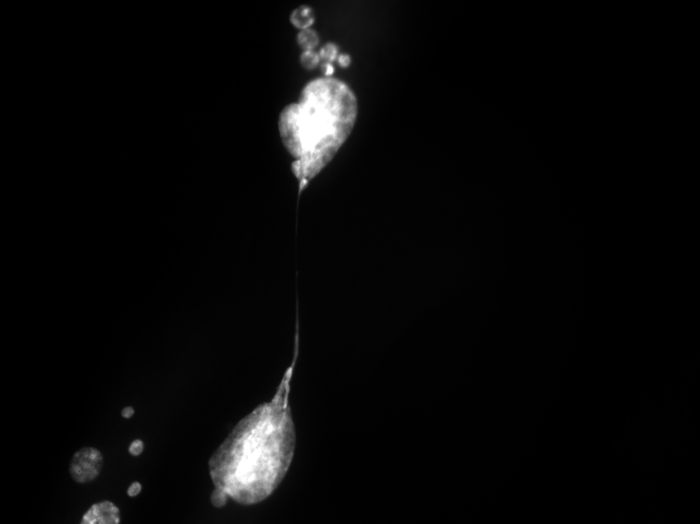

Snapshots of the life of a cell

To achieve such results, Rodier’s research team was able to count on state-of-the-art imaging equipment funded by the Institut du cancer de Montréal.

“Genetically, we were able to reproduce the phenomenon of cellular aging in the laboratory and ensured that all the telomeres of a population of cells became dysfunctional,” said PhD student Marc-Alexandre Olivier, co-first author of the study with former colleague Sabrina Ghadaouia, currently pursuing postdoctoral studies in England. “With our equipment, we then observed in real time what was happening inside each single cell.”